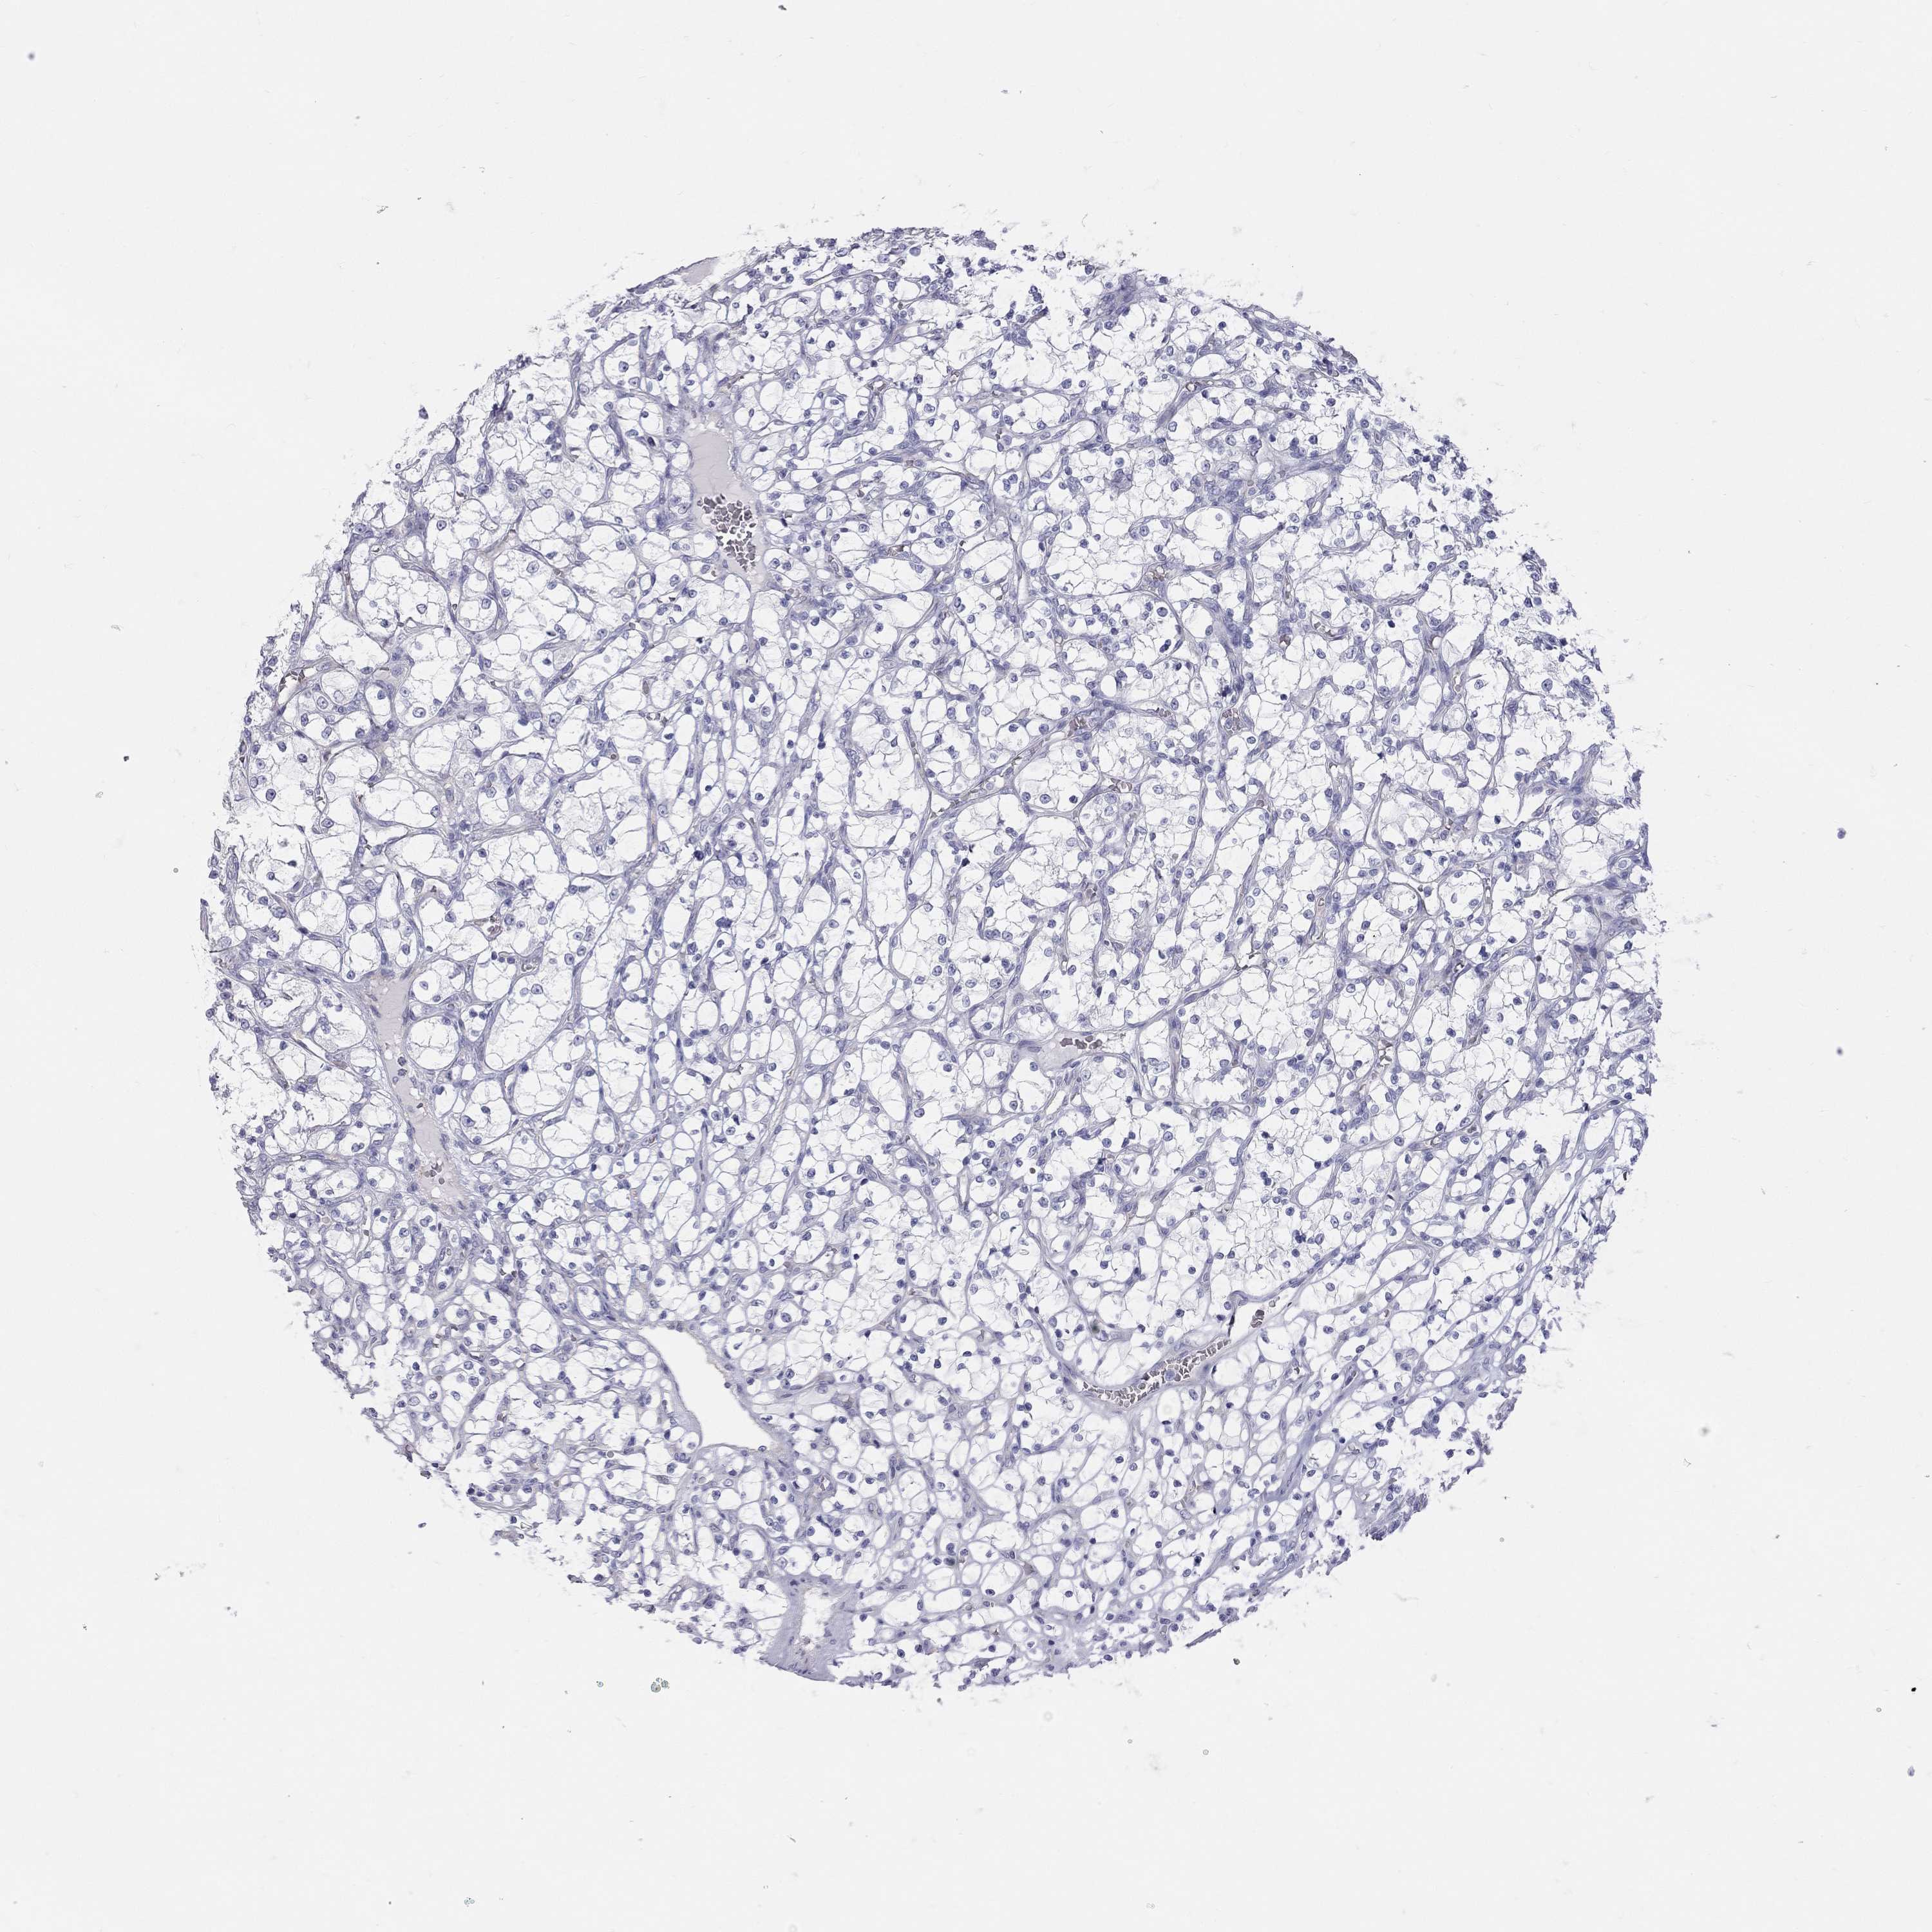

KIDNEY RENAL CLEAR CELL CARCINOMA (TCGA) - Interactive survival scatter ploti

The Survival Scatter plot shows the clinical status (i.e. dead or alive) for all individuals in the patient cohort, based on the same data that underlies the corresponding Kaplan-Meier plots. Patients that are alive at last time for follow-up are shown in blue and patients who have died during the study are shown in red.

The x-axis shows the expression levels (FPKM) of the investigated gene in the tumor tissue at the time of diagnosis. The y-axis shows the follow-up time after diagnosis (years). Both axes are complimented with kernel density curves demonstrating the data density over the axes. The top density plot shows the expression levels (FPKM) distribution among dead (red) and alive patients (blue). The right density plot shows the data density of the survived years of dead patients with high and low expression levels respectively, stratified using the cutoff indicated by the vertical dashed line through the Survival Scatter plot. This cutoff is automatically defined based on the FPKM cutoff that minimizes the p-score. The cutoff can be changed by dragging the vertical line or by entering a cutoff value in the square labeled "Current cut-off".

Under the Survival Scatter plot the p-score landscape (black curve; left axis) is shown together with dead median separation (red curve; right axis). Dead median separation is the difference in median mRNA expression between patients who have died with high and low expression, respectively. It is calculated as follows: median FPKM expression of dead patients with high expression - median FPKM expression of dead patients with low expression. This is intended to aid the user in visually exploring custom cutoffs and the associated p-scores and dead median separation.

Individual patient data is displayed and can be filtered by clicking on one or more of the category buttons on the top of the page. Categories describing expression level and patient information include: high, low, alive, dead, female, male and tumor stages. The scale of the x-axis can be toggled between linear and log-scale by clicking on the "x log" button. Mouse-over function shows TCGA ID, patient information and mRNA expression (FPKM) for each patient.

& Survival analysisi

Kaplan-Meier plots summarize results from analysis of correlation between mRNA expression level and patient survival. Patients were divided based on level of expression into one of the two groups "low" (under cut off) or "high" (over cut off). X-axis shows time for survival (years) and y-axis shows the probability of survival, where 1.0 corresponds to 100 percent.

TDRD6 is not prognostic in Kidney Renal Clear Cell Carcinoma (TCGA)

: 1.29

Average pTPM 1.3

Number of samples 521